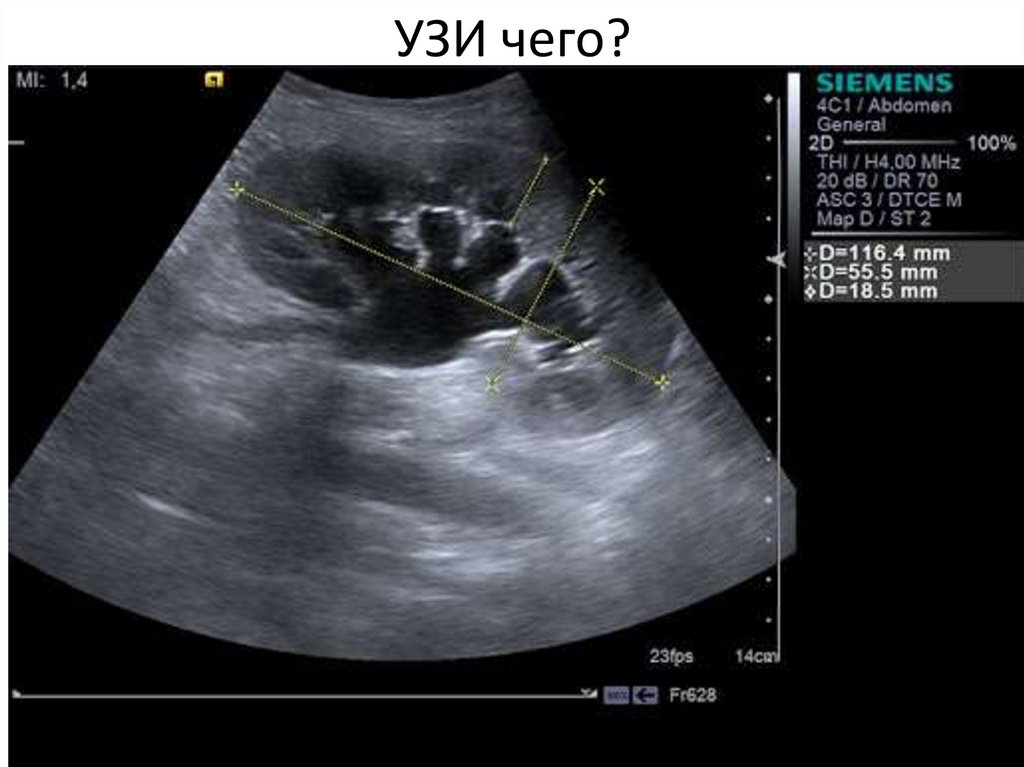

УЗИ чего?

16.